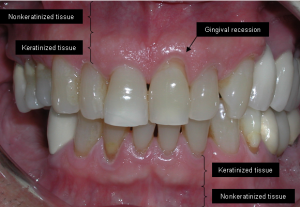

4. Receding Gums:

Gums that are pulling away from the teeth can create pockets where bacteria thrive, leading to further infection.